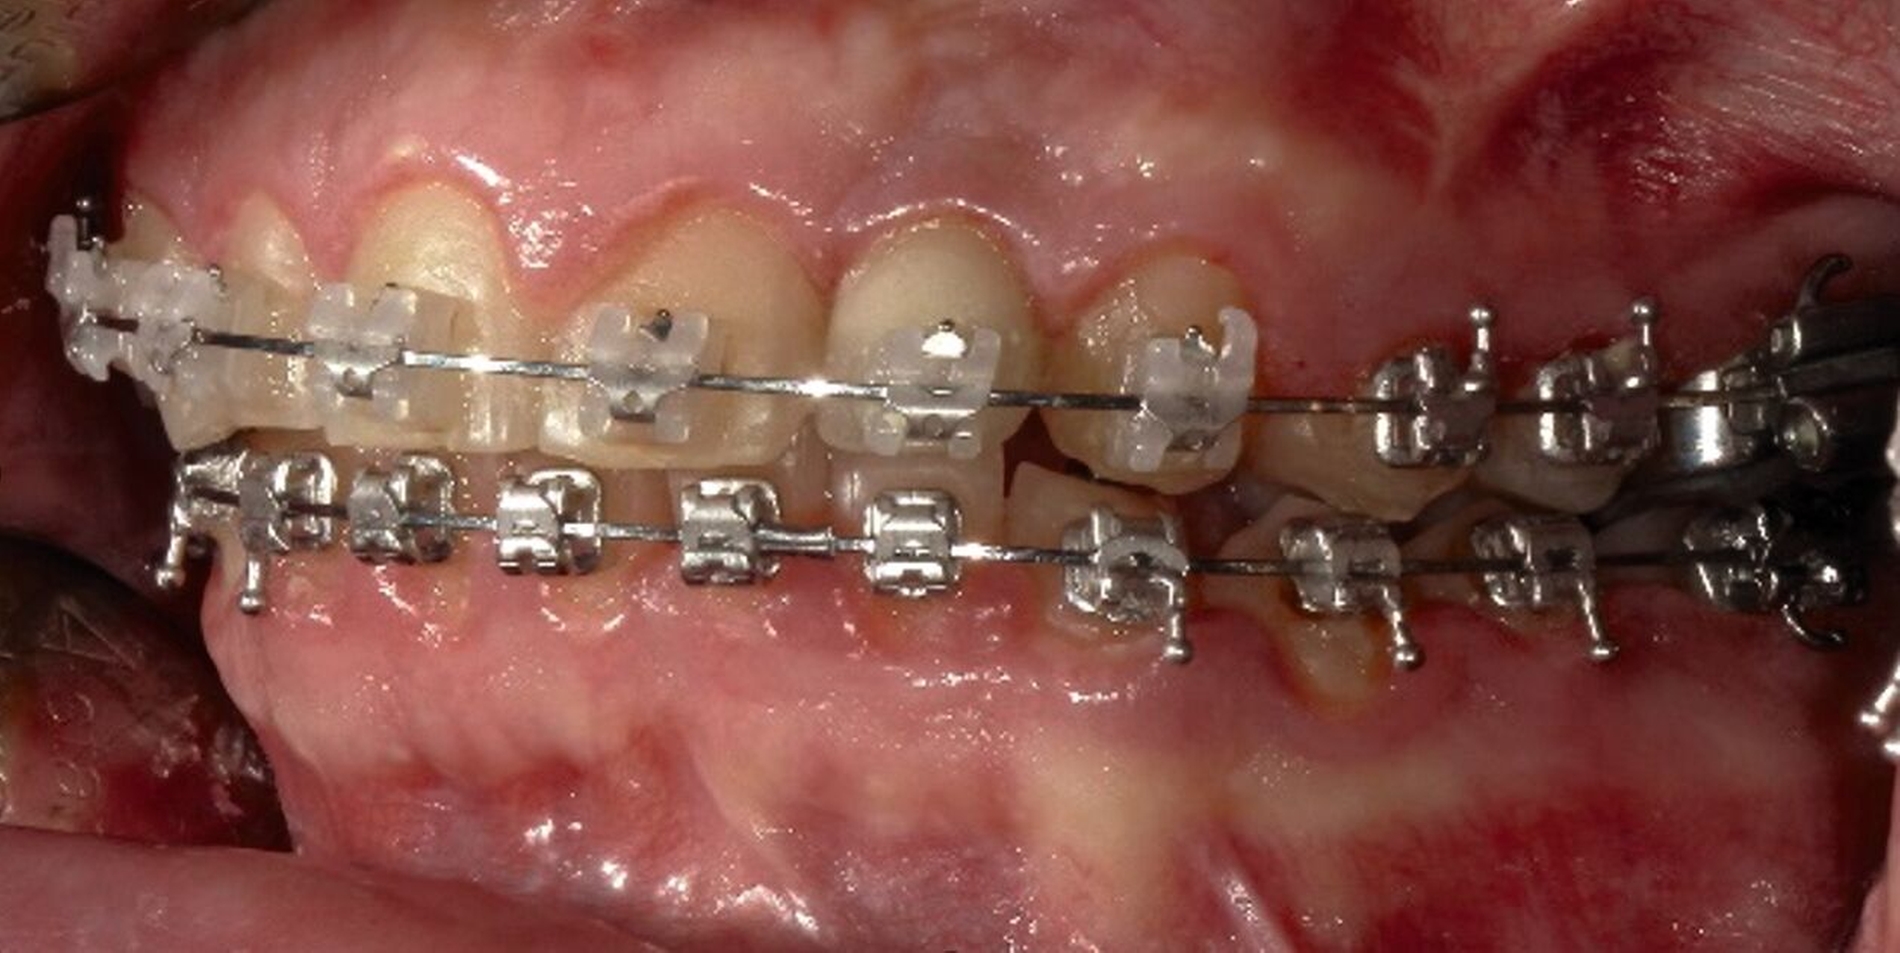

Nach diesem Eingriff schloss sich bis zum 17. Lebensjahr eine kieferorthopädische Therapie bei skelettaler maxillärer Retrognathie an. Der Zahn 22 war nicht angelegt, die Lücke wurde kieferorthopädisch offengehalten. Im Bereich 22 wurden nach Abschluss des Wachstums eine Augmentation durchgeführt und ein zahnärztliches Implantat inseriert. Dennoch konnten die Laterognathie des Oberkiefers mit einer Mittellinienverschiebung von 2,5 mm, der Tiefbiss sowie der Kreuzbiss auf der linken Seite nicht vollständig behoben werden (Abbildungen 1 und 2).

Gemeinsam mit den behandelnden Kieferorthopäden wurde aufgrund des abgeschlossenen Wachstums und der ausgeschöpften nicht-chirurgischen Maßnahmen die interdisziplinäre Indikation zur chirurgischen Korrektur der Dysgnathie gestellt. Anhand einer kephalometrischen Analyse trafen wir gemeinsam mit der Patientin die Entscheidung zur Durchführung einer bimaxillären Umstellungsosteotomie (Abbildung 3).